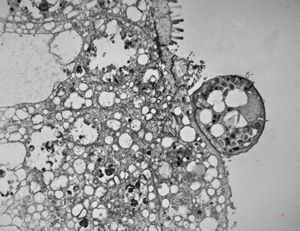

M,33y. | microsporidiosis (or cryptosporidiosis) - duodenum-posttransplantation immunodeficiency (HE and semithin section)

M,33y. | microsporidiosis (or cryptosporidiosis) - duodenum-posttransplantation immunodeficiency